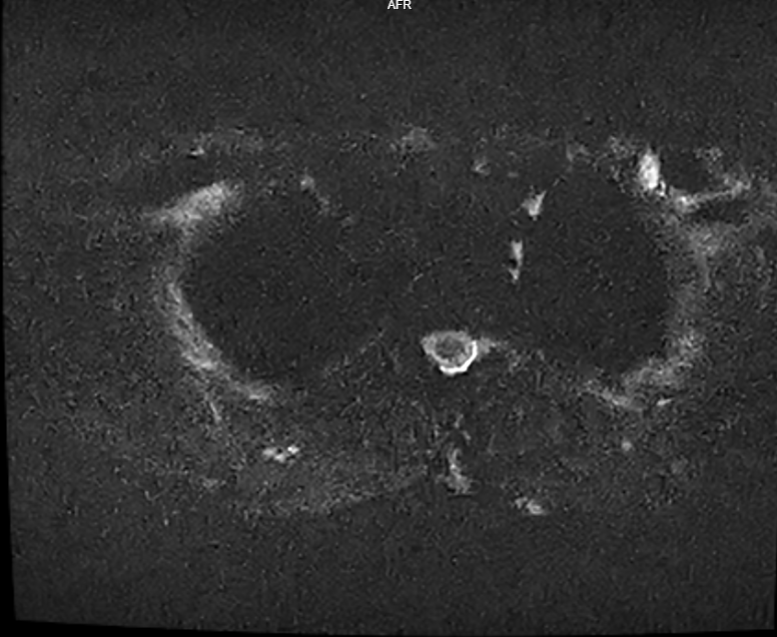

脊髓磁共振定位漏点范围